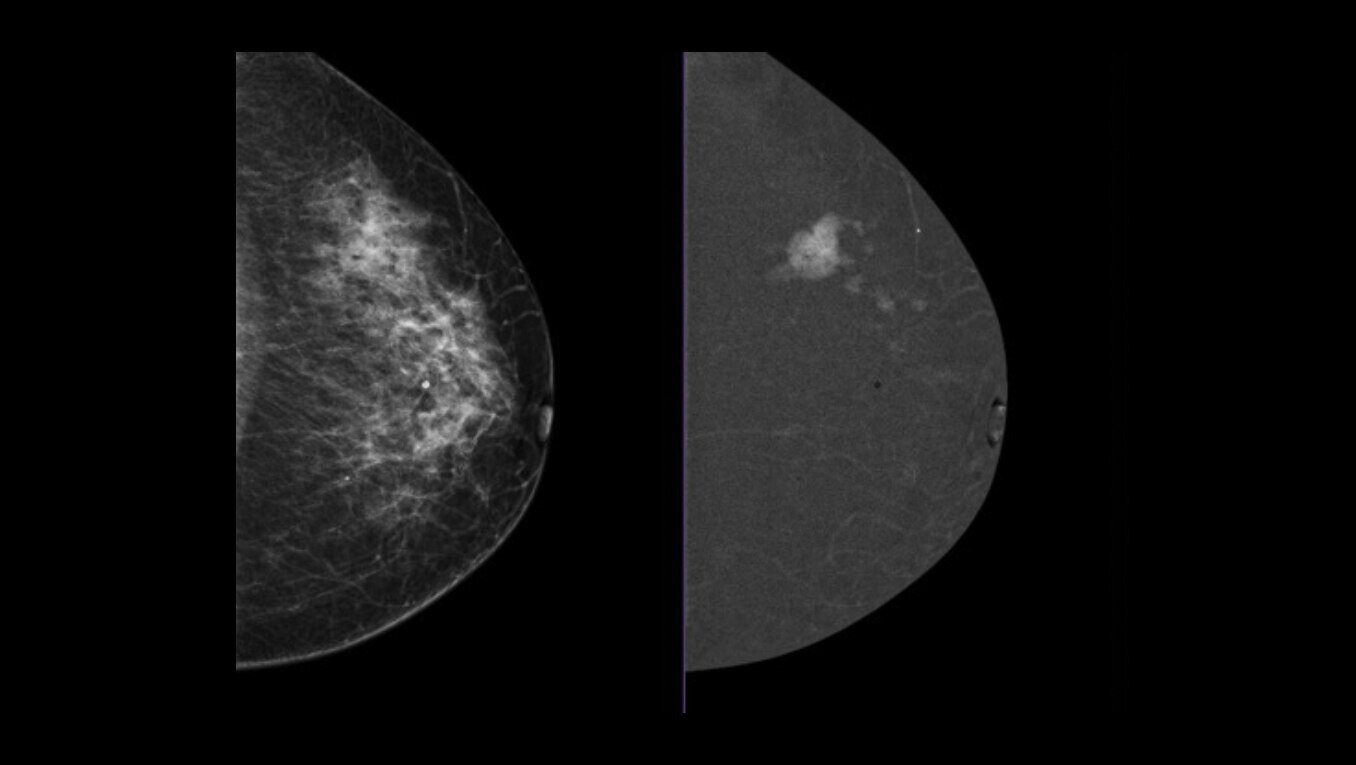

SenoBright™ HD

Contrast-Enhanced Mammography advanced application

Reduces the masking effect of breast tissue to reveal what matters1.